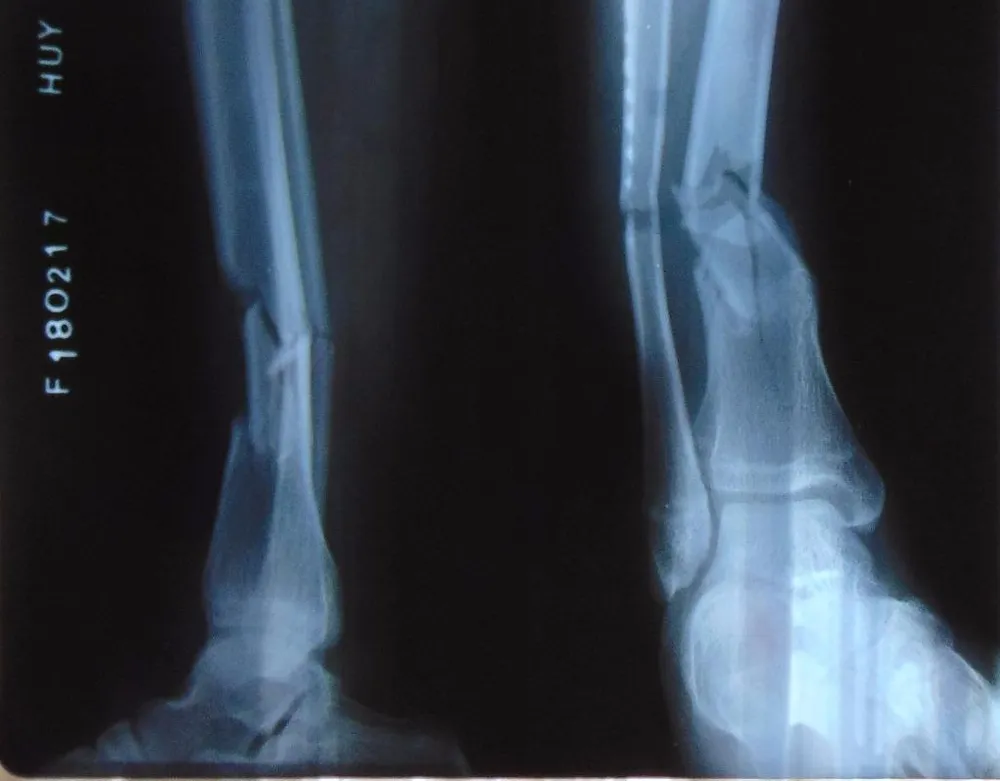

chụp xquang

Kết quả chụp X-quang cho thấy bệnh nhân NTQ bị gãy kín 1/3 dưới hai xương cẳng chân phải. Ảnh: TRẦN NGỌC

Mới đây, BV quận 12 cũng đã phẫu thuật thành công ca gãy kín 1/3 dưới hai xương cẳng chân phải cho bệnh nhân NTQ (16 tuổi, quận 12). Đây cũng là lần đầu BV quận 12 phẫu thuật ca gãy xương phức tạp ở một bệnh nhân trẻ tuổi và đã thành công.